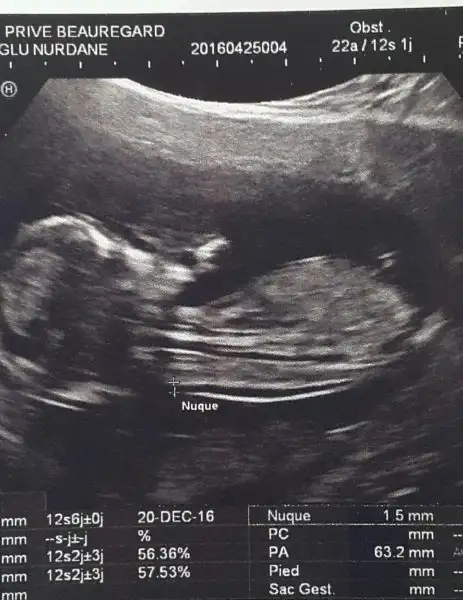

Biz bebişimizi gorduk bugun :) cok tatli bebegim benim parmagini emiyorducok sukur ense kalinligi flan iyi bir sorun yok dedi doktor 2.li tarama icin kan verdim. Sonuclarim direk doktora gidecek gerekirse o beni arayacak. Bebegimin kalbi 154 atiyordu. Benim tahmince erkek. Cunku oglumdada oyleydi cinsiyeti sordum . Genital nubunu gosterdi. Dedim erkek mi ? Oda kesin bisey diyemem dedi. Hayirlisi olsun ama bana gore erkek boyle iste kizlar biz iyiyiz. RAbbim butun hamilelere guc kuvvet versin sorunu olanlara sifa versin. Hayirlisiyla şu mübarek Ramazan ayinda hersey gonlumuzce olsun ) bu arada ben oruc tutmuyorum doktorum sakın tutma dedi yasafi yedik yani kizlar sizde bi tahminde bulunun resmi ekledim

Başka bir dra danışmakla en iyisini etmişsinz ense kalınlığına ne dedi

cnm ense kalınlığı nasıldı ki? üzülme o sadece bir tarama testi tanı değil.Kızlar moralim çok bozuk ikili test sonucuma doktor riskli dedi.Amniyosentez önerdi.